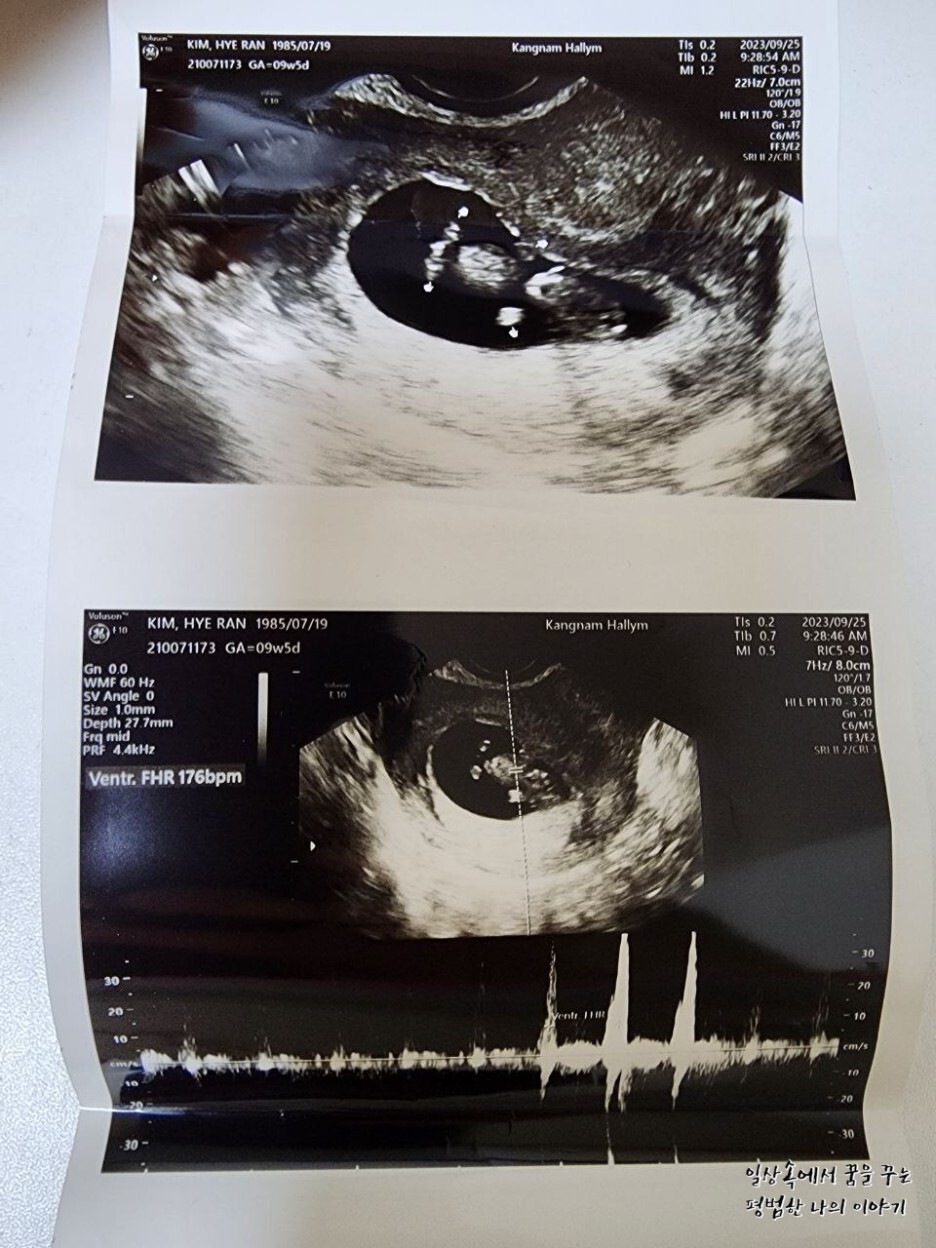

2023년 9월 25일(월요일)

FHR(Fetal Heart Rate, 심장박동 수): 176bpm

소견: 무척 활발해서 한시도 가만히 있지 않음